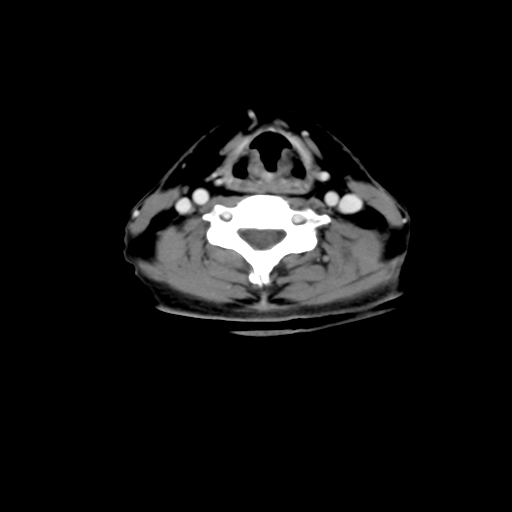

标题: CT24019:男,45岁,发现颈部肿物5个月。 [打印本页]

男,45岁,发现颈部肿物5个月,彩超示:双侧颈部及下颌部软组织增厚。

考虑双侧颈项部良性对称性脂肪增多症。

双侧颈项部脂肪沉积